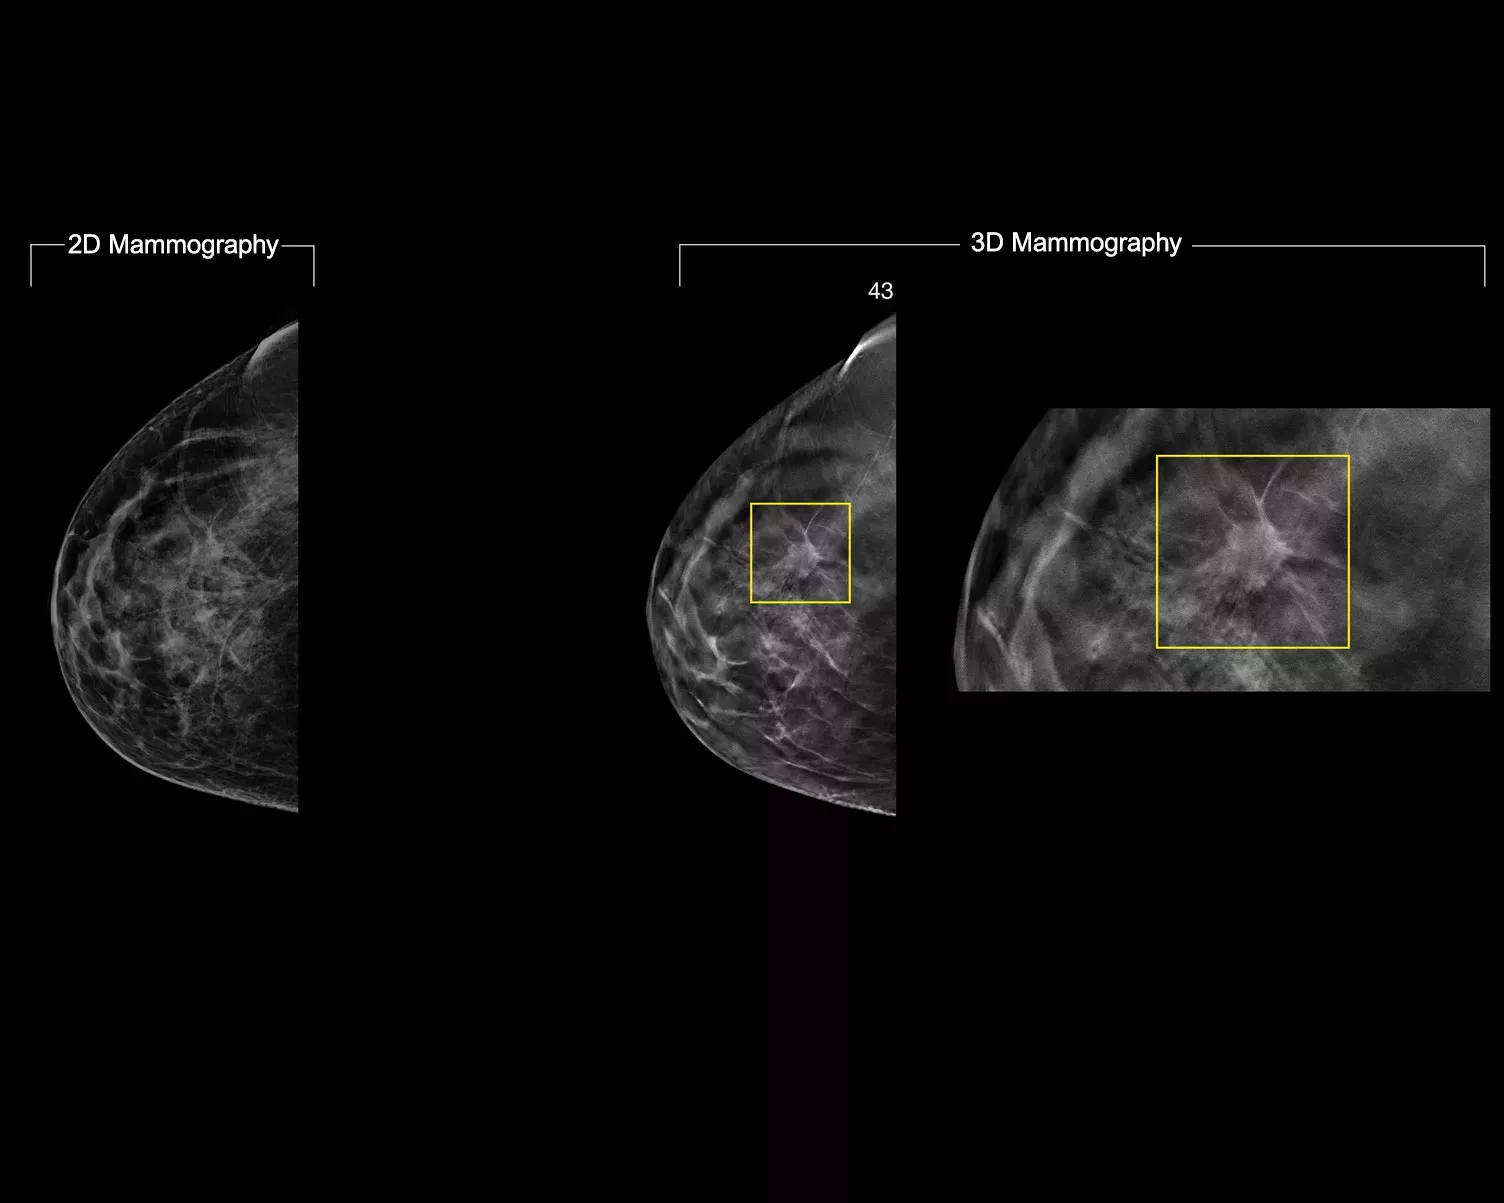

Un algoritmo di deep-learning studiato per coadiuvare le prestazioni diagnostiche dei medici radiologi e individuare i tumori al seno1-3 dalle immagini di tomosintesi ottenute con i sistemi mammografici Dimensions® Hologic. L'algoritmo individua le lesioni probabilmente riconducibili a un tumore della mammella, analizzando ogni sezione della serie di immagini di tomosintesi. Le aree sospette vengono evidenziate sulla stazione di lavoro del medico radiologo per una lettura immediata e un ausilio nell'interpretazione.

Uno studio mostra un miglioramento del 9% della sensibilità di lettura.1.2 Funziona su immagini di tomosintesi standard e ad alta risoluzione, sovrapponendo le informazioni su SmartSlice 3DQuorum e immagini 2D sintetiche.

L'algoritmo cerca 3 gruppi principali di lesioni sospette: calcificazioni, masse, densità con distorsioni e le loro combinazioni. I risultati possono variare in base alla stazione di lavoro usata per la refertazione.